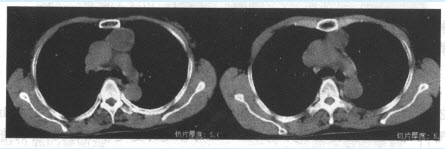

(单选题)该患者的胸部CT如下图,前纵隔内类圆形肿物,密度稍低于骨骼肌密度,最可能的诊断是()

A:神经源性肿瘤

B:畸胎瘤

C:胸腺瘤

D:淋巴瘤

E:脂肪瘤

F:转移瘤